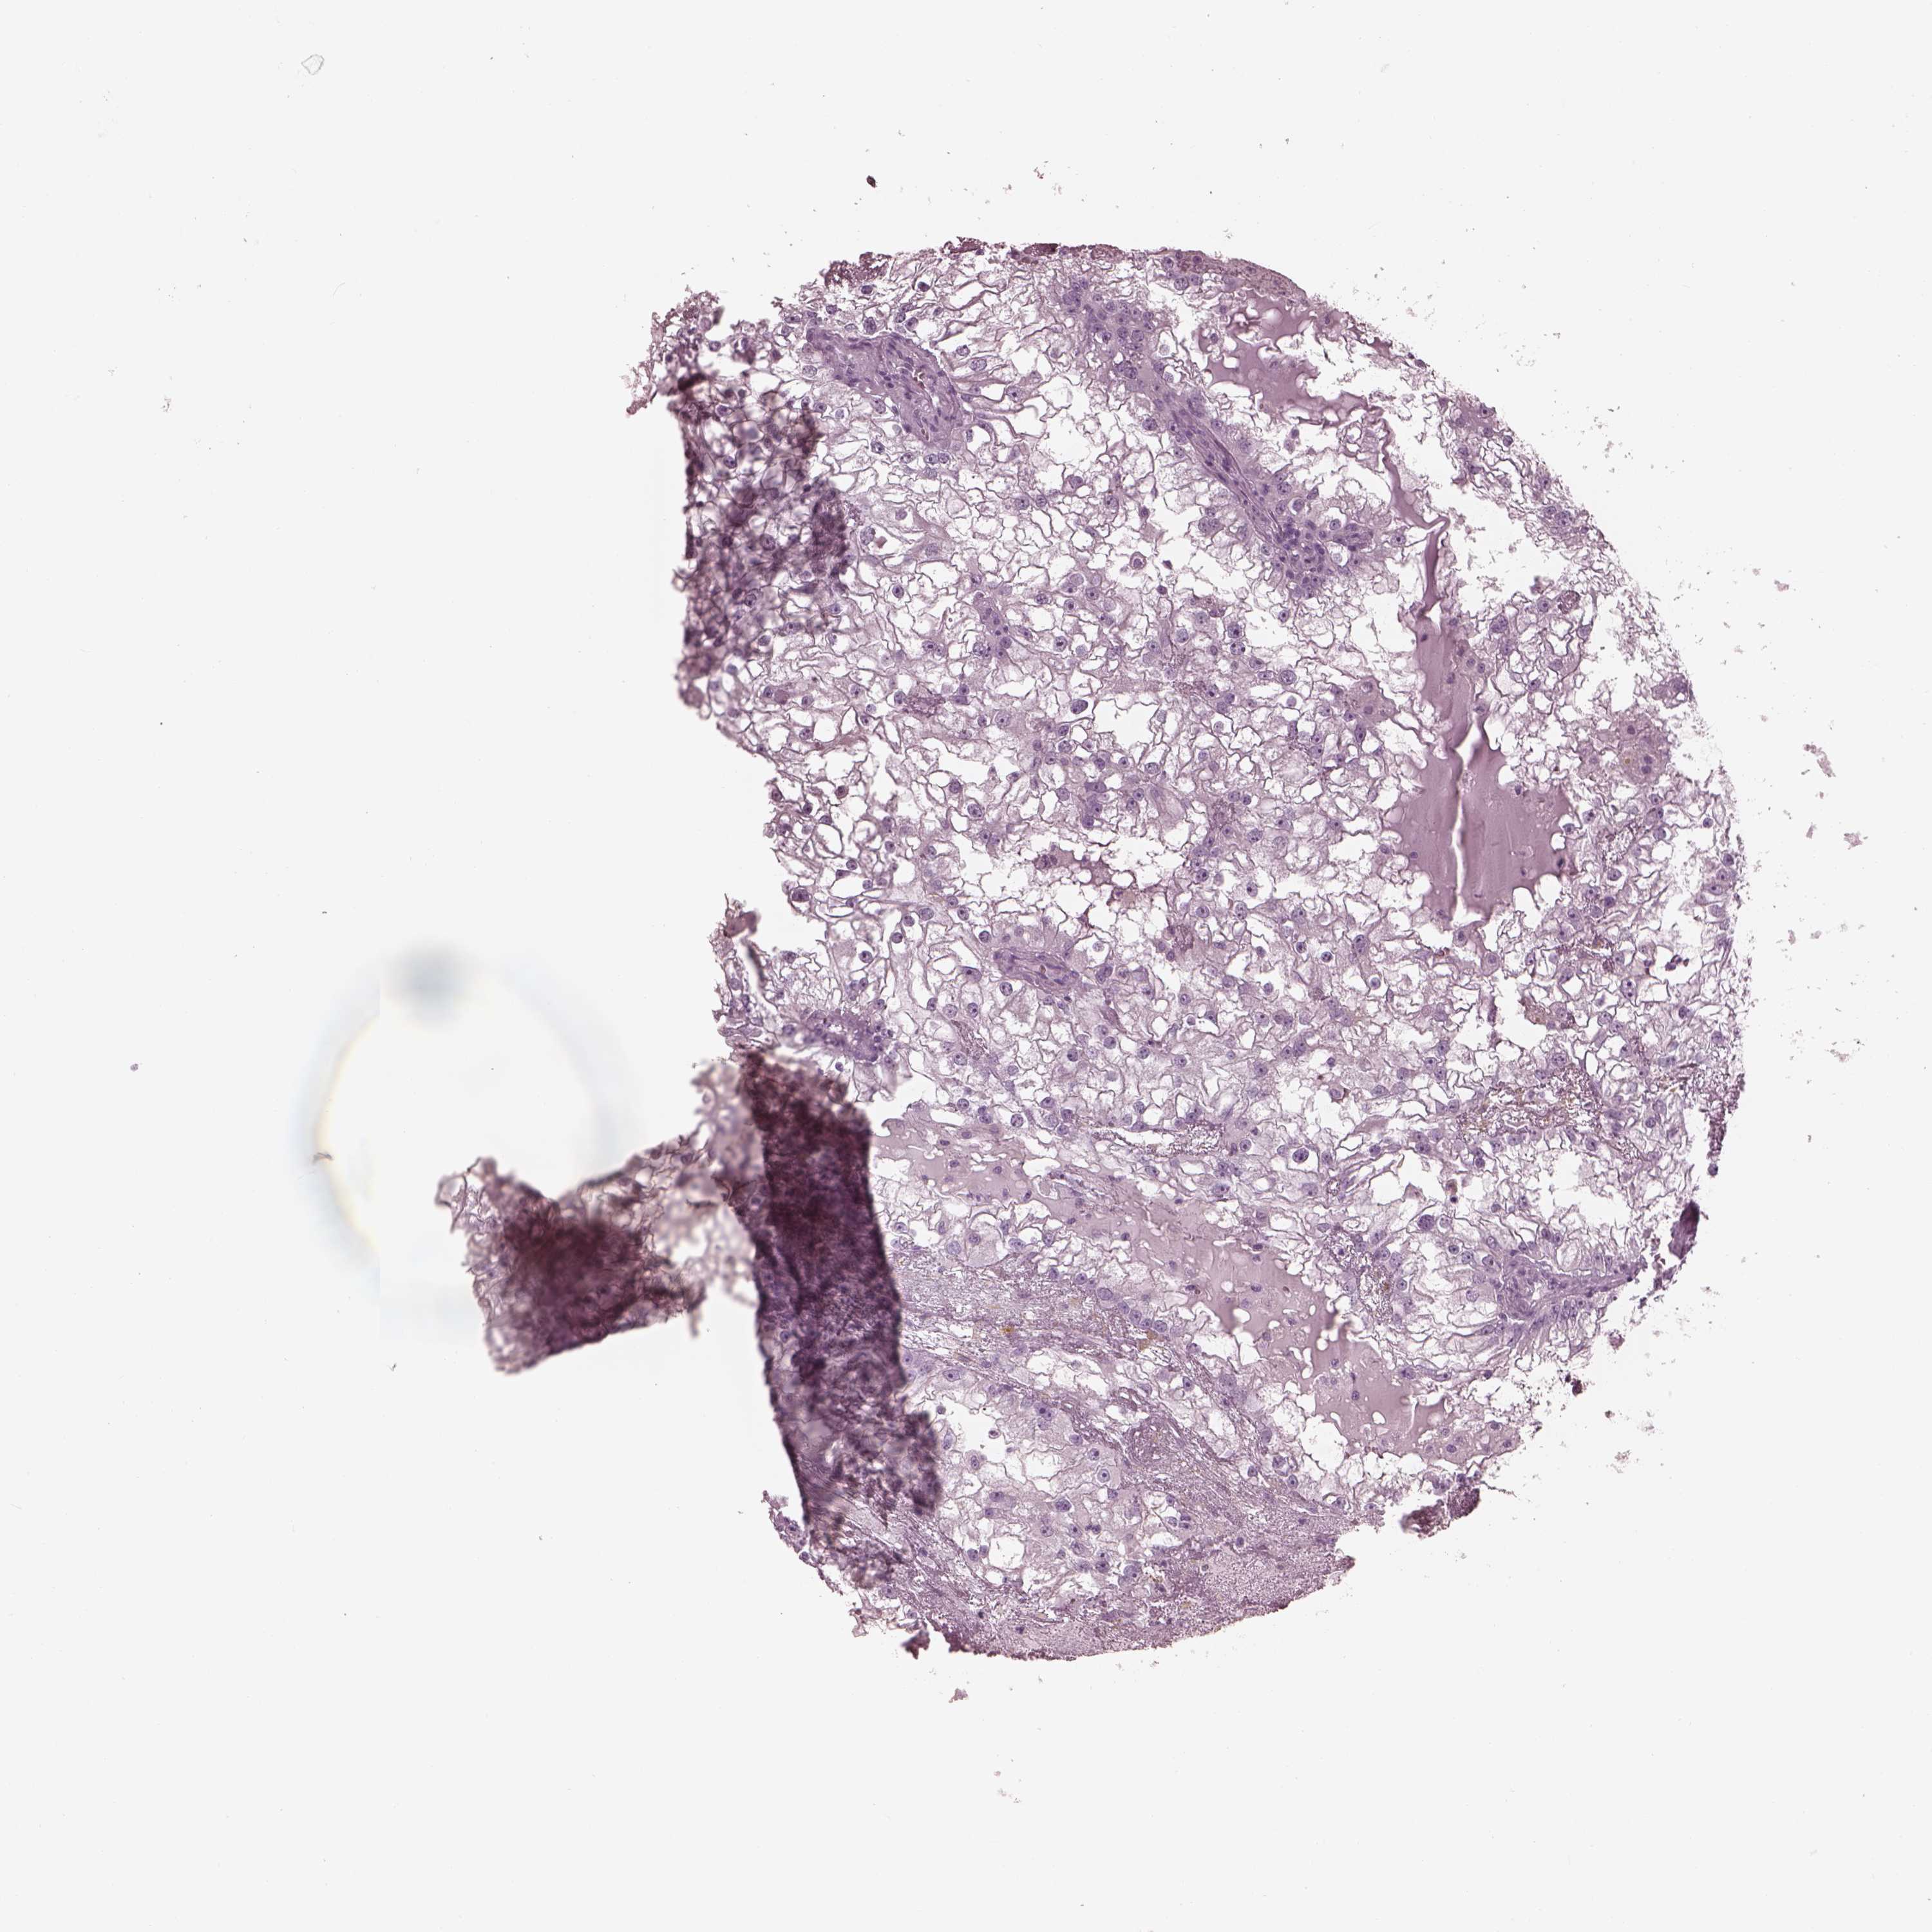

KIDNEY RENAL PAPILLARY CELL CARCINOMA (TCGA) - Interactive survival scatter ploti

The Survival Scatter plot shows the clinical status (i.e. dead or alive) for all individuals in the patient cohort, based on the same data that underlies the corresponding Kaplan-Meier plots. Patients that are alive at last time for follow-up are shown in blue and patients who have died during the study are shown in red.

The x-axis shows the expression levels (FPKM) of the investigated gene in the tumor tissue at the time of diagnosis. The y-axis shows the follow-up time after diagnosis (years). Both axes are complimented with kernel density curves demonstrating the data density over the axes. The top density plot shows the expression levels (FPKM) distribution among dead (red) and alive patients (blue). The right density plot shows the data density of the survived years of dead patients with high and low expression levels respectively, stratified using the cutoff indicated by the vertical dashed line through the Survival Scatter plot. This cutoff is automatically defined based on the FPKM cutoff that minimizes the p-score. The cutoff can be changed by dragging the vertical line or by entering a cutoff value in the square labeled "Current cut-off".

Under the Survival Scatter plot the p-score landscape (black curve; left axis) is shown together with dead median separation (red curve; right axis). Dead median separation is the difference in median mRNA expression between patients who have died with high and low expression, respectively. It is calculated as follows: median FPKM expression of dead patients with high expression - median FPKM expression of dead patients with low expression. This is intended to aid the user in visually exploring custom cutoffs and the associated p-scores and dead median separation.

Individual patient data is displayed and can be filtered by clicking on one or more of the category buttons on the top of the page. Categories describing expression level and patient information include: high, low, alive, dead, female, male and tumor stages. The scale of the x-axis can be toggled between linear and log-scale by clicking on the "x log" button. Mouse-over function shows TCGA ID, patient information and mRNA expression (FPKM) for each patient.

& Survival analysisi

Kaplan-Meier plots summarize results from analysis of correlation between mRNA expression level and patient survival. Patients were divided based on level of expression into one of the two groups "low" (under cut off) or "high" (over cut off). X-axis shows time for survival (years) and y-axis shows the probability of survival, where 1.0 corresponds to 100 percent.

Survival analysis data not available.

TCGA RNA samplesi

RNA-seq data is reported as average FPKM (number Fragments Per Kilobase of exon per Million reads), generated by the The Cancer Genome Atlas (TCGA) .

Normal distribution across the dataset is visualized with box plots, shown as median and 25th and 75th percentiles. Points are displayed as outliers if they are above or below 1.5 times the interquartile range. FPKM values of the individual samples are presented next to the box plot.

Average pTPM 0.0

Number of samples 282